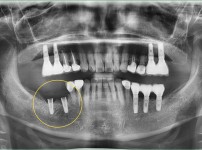

2

BEFORE

AFTER

클릭 해주세요.

임플란트 재식립 사례

임플란트